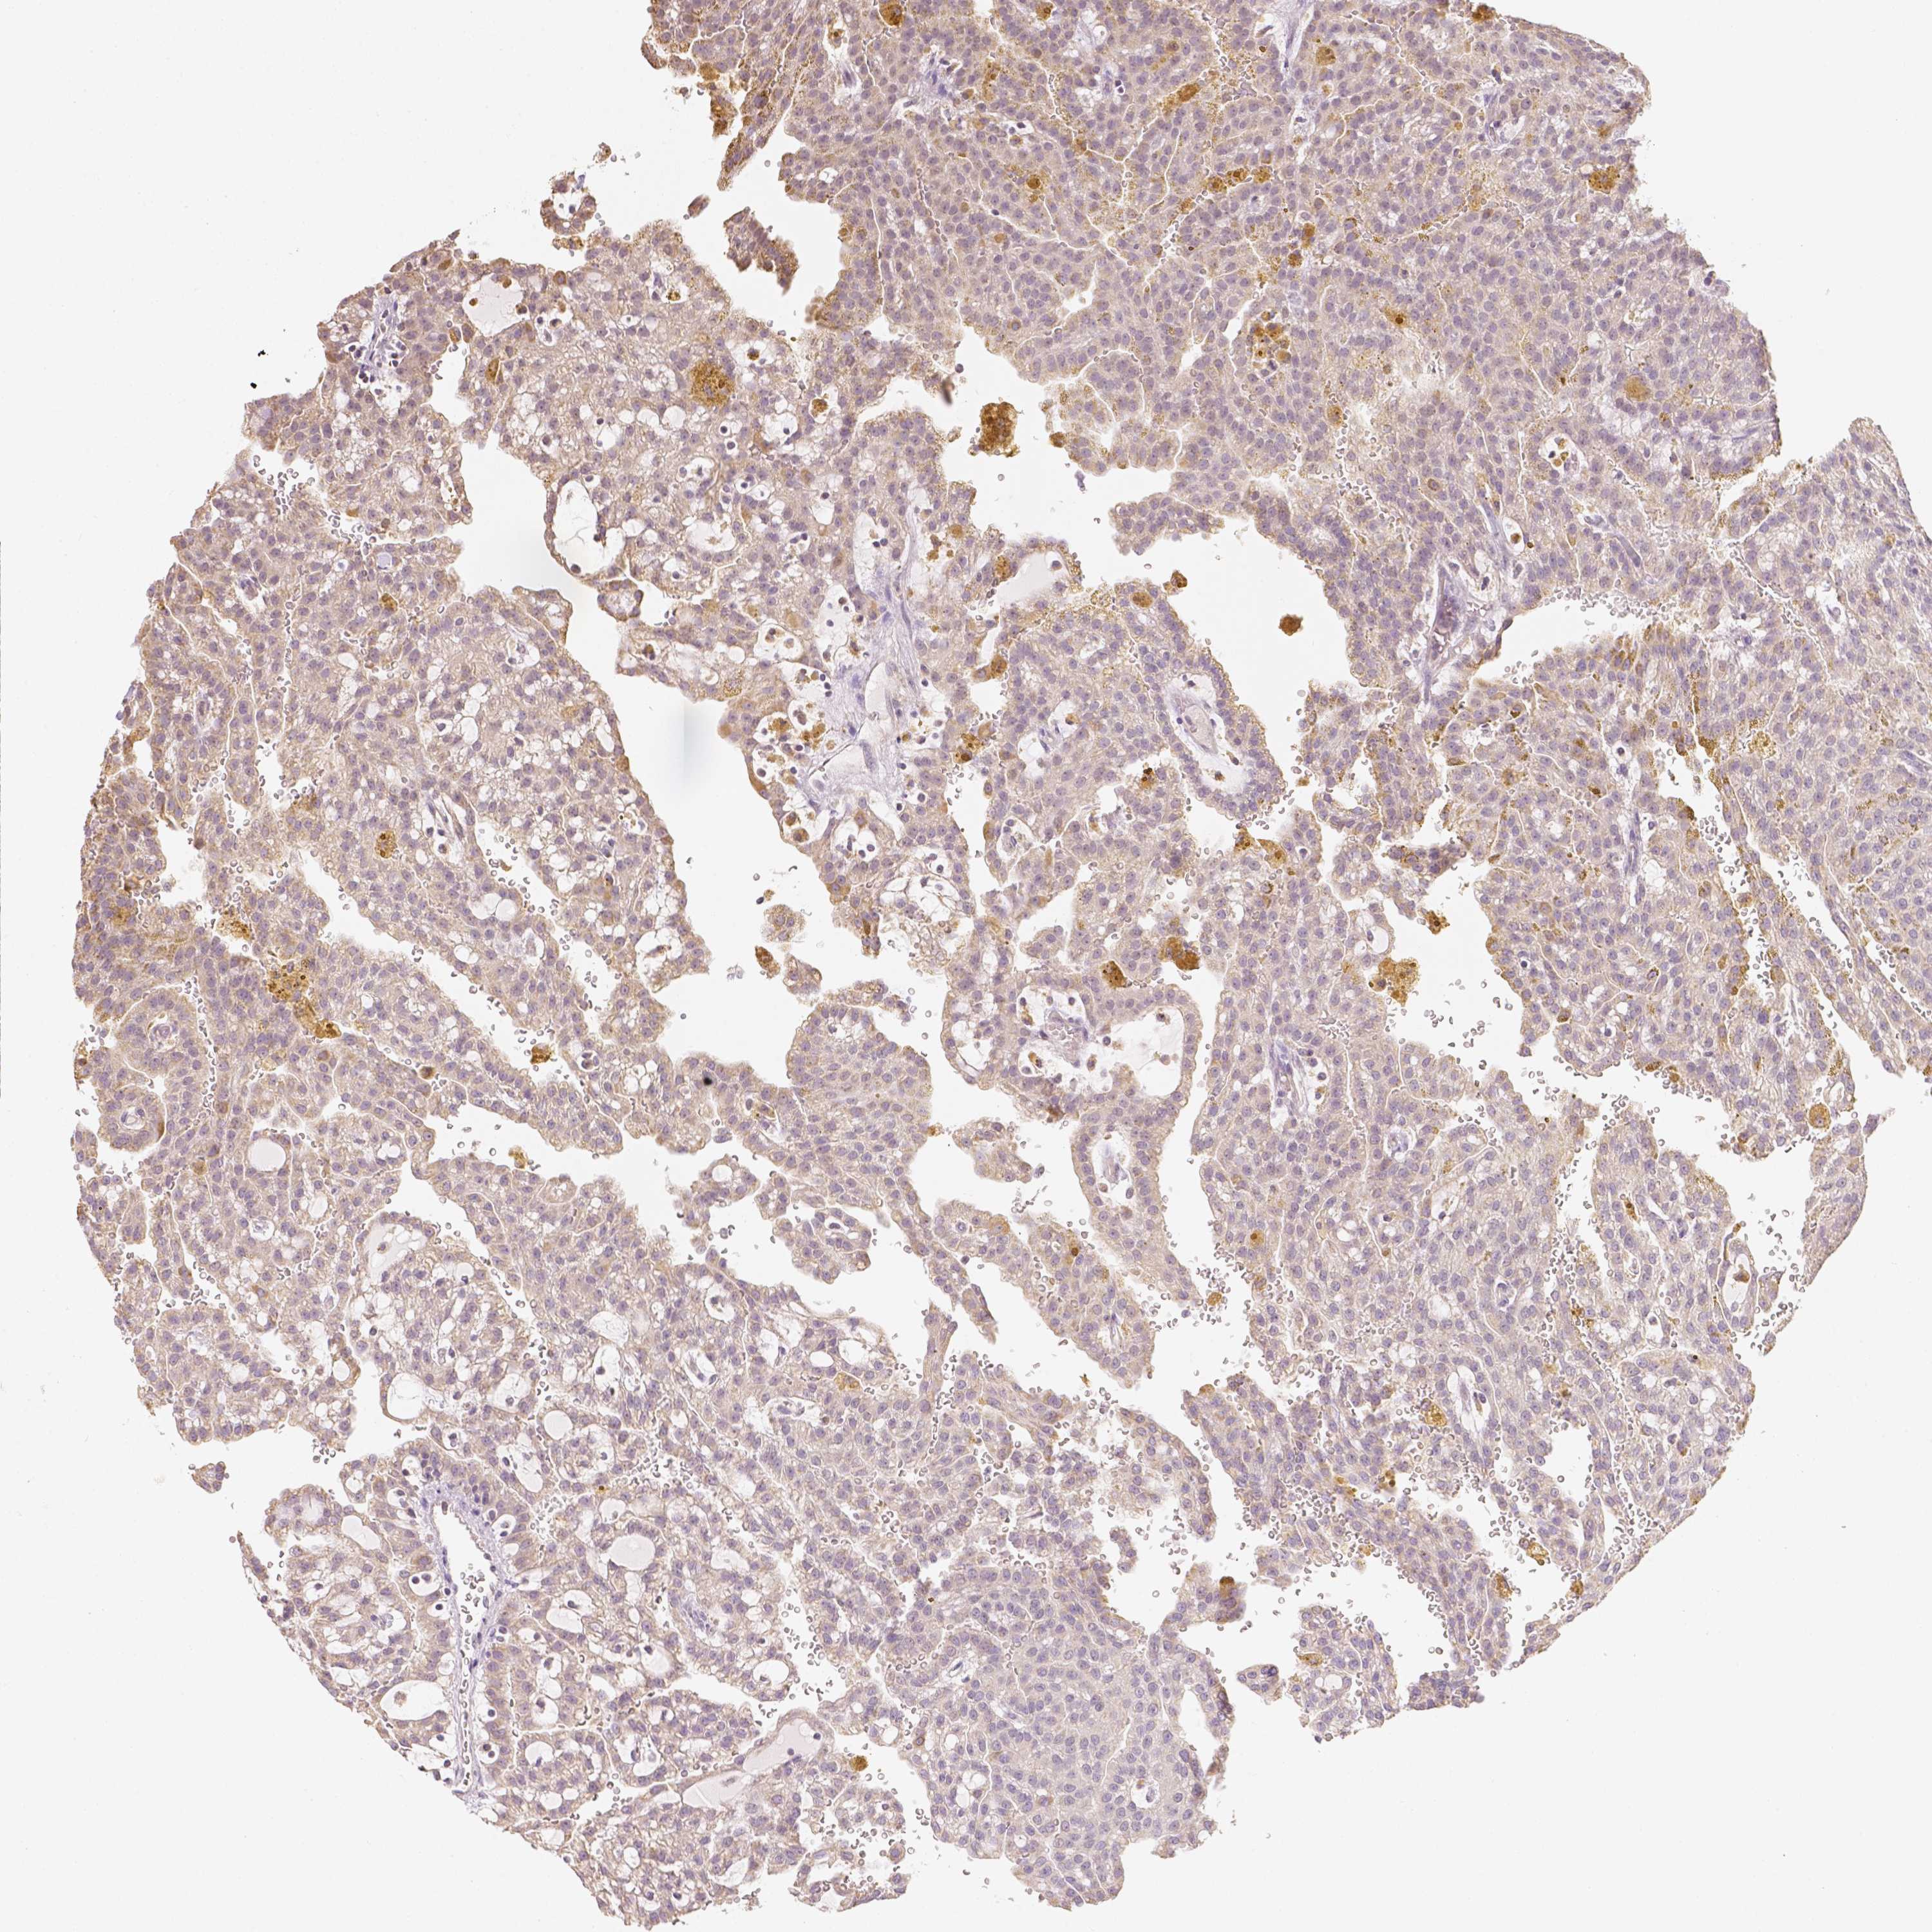

CANCER RENAL CANCER Show tissue menu

KICH TCGA KIRC TCGA KIRC VALIDATION KIRP TCGA PROTEIN RCC CPTAC PROTEIN EXPRESSION